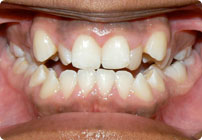

Antes

Caso: 11 años

Adolescente: Clase II

Mordida Cruzada Posterior

Sin extracción

Sin uso de expansores

6 alambres superiores

5 alambres inferiores

Sin uso de elásticos

Retenedores: Interior Fijo de TMA y Hawley en superior

Tiempo de tratamiento: 14 Visitas